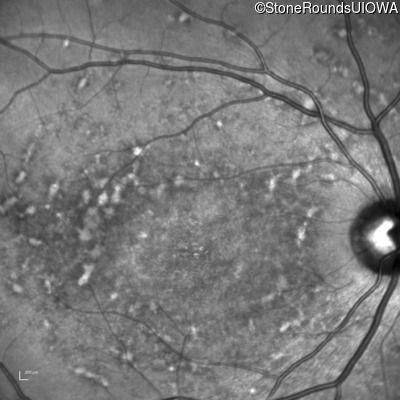

Infrared Fundus Photograph - Right - 20/125 -1

Exemplar